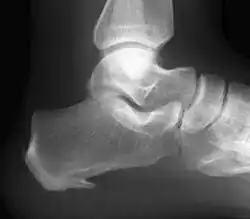

Plantarfasziitis ist eine schmerzhafte Reizung der namensgebenden Plantarfaszie an der Fußsohle. Die Plantarfaszie oder auch Aponeurosis plantaris ist eine vom Fersenbein ausgehende und zur Fußspitze fächerförmig verlaufende Faszienplatte. Bei einer chronischen Reizung des Faszienansatzes am Fersenbein kann es zu Kalziumeinlagerungen kommen. Die resultierende Veränderung imponiert im Röntgenbild als vermeintlicher Fersensporn. Im Gegensatz zur schmerzhaften Plantarfasziitis stellt der Fersensporn an der Fußsohle einen häufig symptomlosen Zufallsbefund bei der Röntgendiagnostik des Fußes dar.[1][2][3][4]

50 Prozent aller Röntgenaufnahmen zeigen bei Plantarfasziitis-Patienten einen Fersensporn, das Ergebnis einer Kalziumeinlagerung in die Sehne. Dieser Fersensporn ist üblicherweise am Ursprung des Musculus quadratus plantae;[7] auch am Musculus abductor hallucis oder seltener an den Musculus abductor digiti minimi können Kalzifizierungen am Sehnenansatz (Enthesiopathie) gesehen werden.[10] Umgekehrt wird der Fersensporn auch bei 13 Prozent aller Röntgenaufnahmen gesehen, die nicht wegen Plantarfasziitis erstellt wurden.[7] Der Fersensporn wird als Folgeerkrankung aufgrund von Zugbelastung und nicht als Ursache der Plantarfasziitis angesehen.[10] Ermüdungsbrüche und manche Tumoren können unter Umständen entdeckt werden und auf eine andere Ursache als Plantarfasziitis für Fersenschmerz hinweisen.[5]